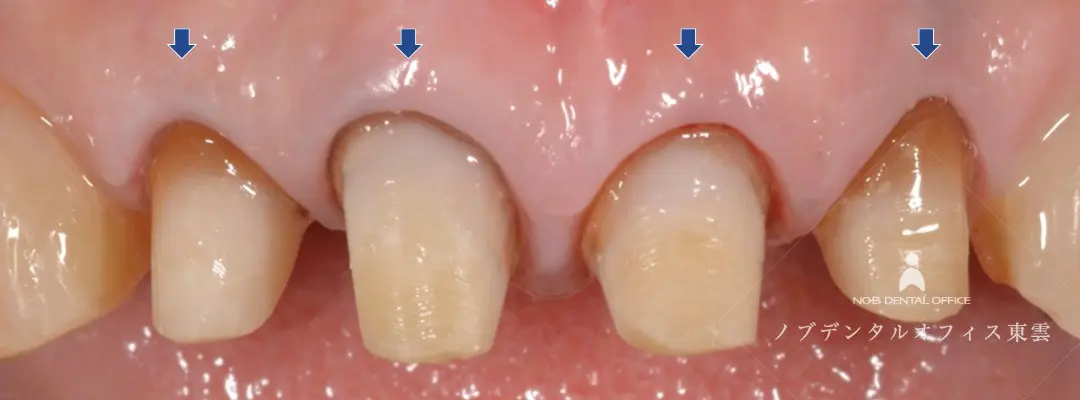

前歯のかぶせ物をジルコニアで再治療した症例(50代女性)

「前歯4本の色が気になる」とご来院された患者様です。

治療前は、前歯の歯ぐきとかぶせ物の間に段差があるため清掃・お手入れが難しく、虫歯や歯周病のリスクが高い状態でした。

また、かぶせ物の土台として入っていたメタルコアにもすき間があるように(左下写真)、歯の奥側にも感染があり、根管治療・土台の治療も行いました。

さらに、前歯の仕上がりをより自然に仕上げるために、歯ぐきの位置をそろえる処置も行いました。

| 期間 | 約6ヶ月 |

|---|---|

| 費用 | オールセラミッククラウン(ジルコニア) 187,000円×4箇所(税込) 保険適応外 |

| リスク | ・経年的に摩耗が起こることがあります。 ・強い噛みしめや歯ぎしりにより、欠けたり外れる可能性があります。 ・歯ぐきの状態によっては境目が見えてくる場合があります。 ・清掃状態や生活習慣によっては境目から虫歯や歯周病が起こることがあります。 |